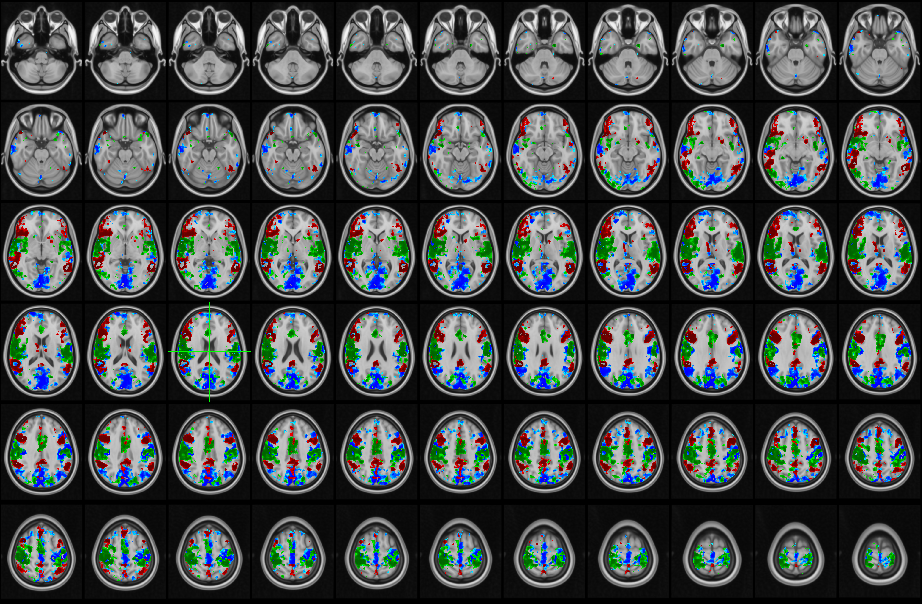

Resting state fMRI emotion tracking

The three dimensions demonstrate strong, consistent, and fully dissociable brain signatures that replicate across participants. Motivation (Red) reliably engages frontostriatal and executive networks; Valence (Blue) shows a distinct rightward pattern in sensory–limbic circuitry; and Activation (Green) produces robust suppression of posterior default-mode regions alongside clear salience-network modulation.